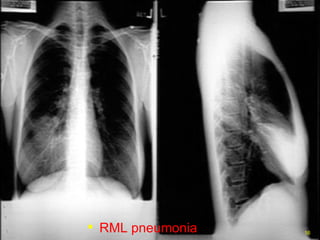

RML pneumonia